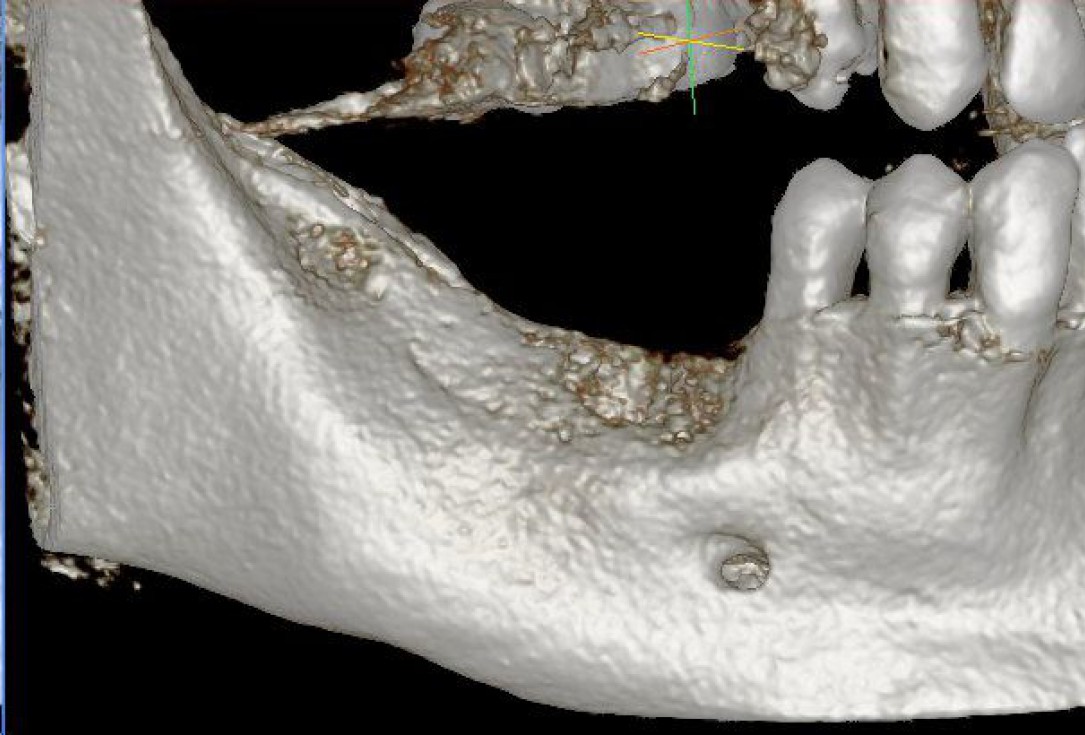

01/28 - Model of the initial defect computed from a CBCT scan - buccal viewThree-dimensional augmentation with maxgraft® cortico - Dr. R. Würdinger